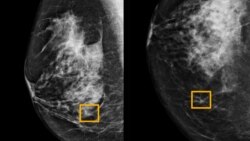

A yellow box indicates where an artificial intelligence (AI) system found cancer hiding inside breast tissue, in an undated photo released by Northwestern University in Chicago, Jan. 1, 2020.